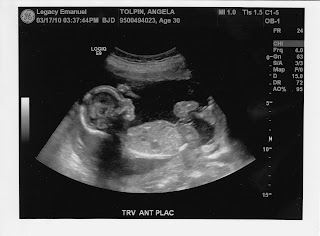

Ultrasound Results